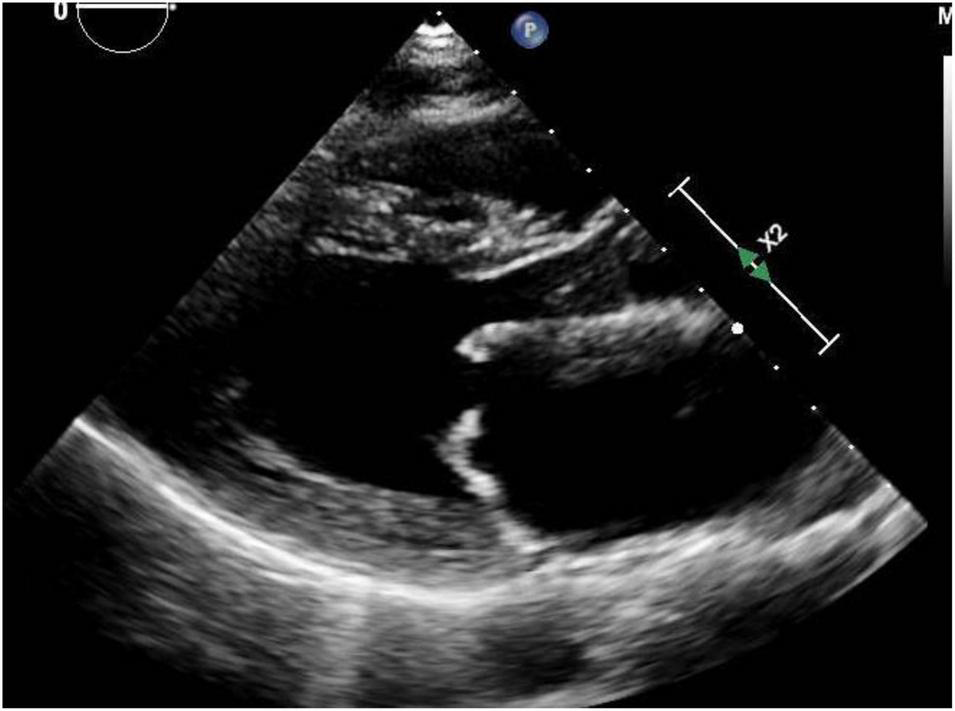

Mitral stenosis most commonly occurs because of rheumatic heart disease, uncommon in developed countries but an important cause in developing nations and in major cities with significant immigrant populations (Figure 2). Congenital mitral stenosis due to parachute mitral valve is rare, and uncommonly seen in adult patients without prior repair. Heart failure symptoms related to mitral stenosis may appear when the mitral valve orifice area is reduced to < 2 cm2 (27). The increased stroke volume and cardiac output of pregnancy may unmask previously asymptomatic mitral valve disease (24, 28). The increasing transmitral valve gradient during pregnancy may lead to pulmonary vascular congestion and pulmonary hypertension. Moreover, the increased heart rate associated with pregnancy limits diastolic filling which further worsens pulmonary edema (29).

FIGURE 2

Mitral stenosis: Representative parasternal long axis view during showing mitral stenosis in a woman with rheumatic heart disease. Both leaflets are affected with thickening and also restriction of their movement.